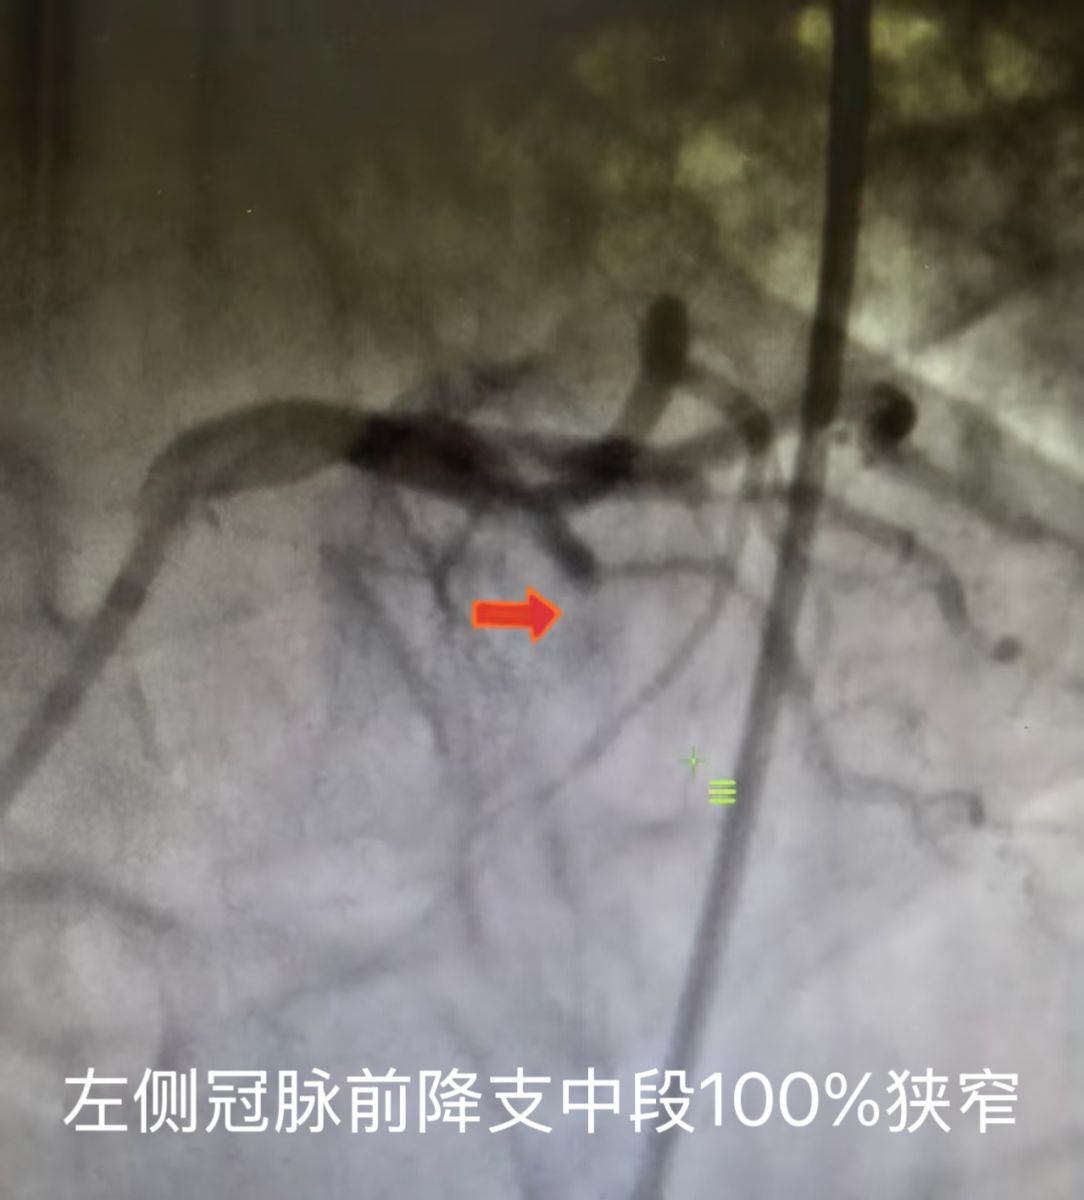

第二抢救小组:以丛占春主任为首的团队立即实施冠脉介入手术,在介入手术期间,李先生多次出现了心律失常,在生死时速的转瞬间,丛主任凭借扎实的专业功底和丰富的临床经验,迅速为李先生穿刺右侧股动脉,冠脉造影显示:左侧冠脉前降支中段100%狭窄。随即植入了两枚心脏支架,李先生的堵塞的心脏血管被开通,心脏血管血流通畅无阻。